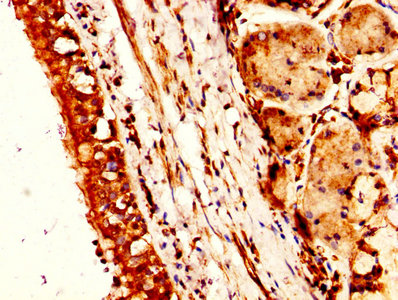

ApplicationELISA, WB, IHC; Recommended dilution: WB:1:1000-1:5000, IHC:1:200-1:500